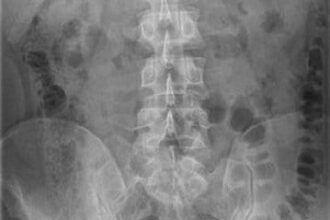

tù nhân nuốt điện thoại

Úc: Chán đời nuốt luôn điện thoại vào bụng